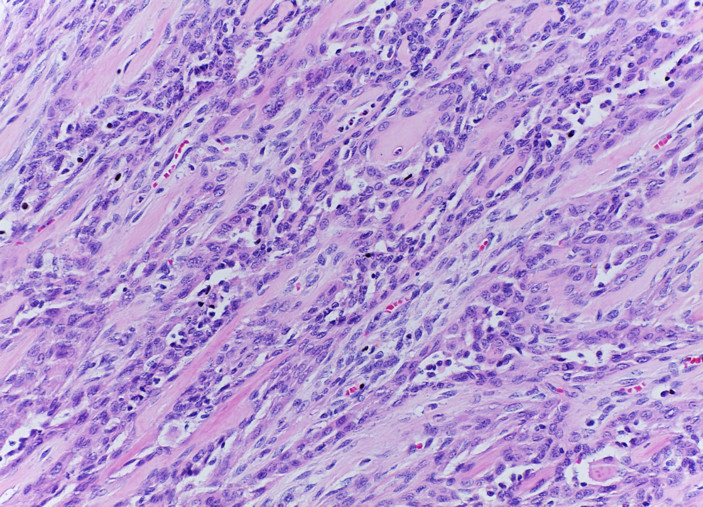

Mujer de 61 años con padecimiento de 1 año de evolución caracterizado por tumor en cuello, disfonía y disfagia progresiva.

Se le realizó tiroidectomía total y laringectomía.

Tumor de células fusiformes con diferenciación semejante a timo (SETTLE por sus siglas en inglés).